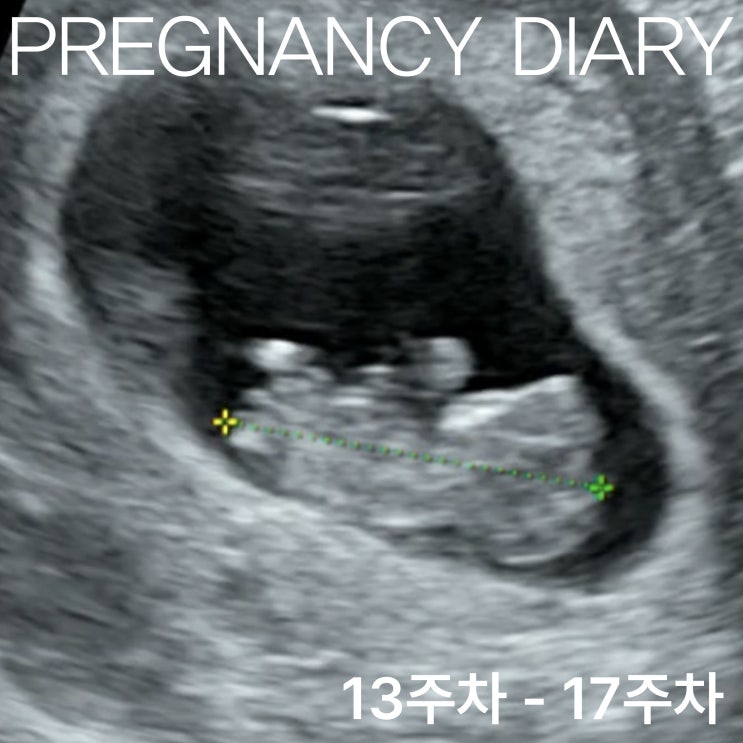

[임신 일기] 13주차에서 17주차, 이사 준비 그리고 니프티검사

시간은 흐르고, 나는 살이 계속 찐다. 2023년 4월, 인테리어 공사가 본격적으로 시작되었고 시부모님 집과 ...